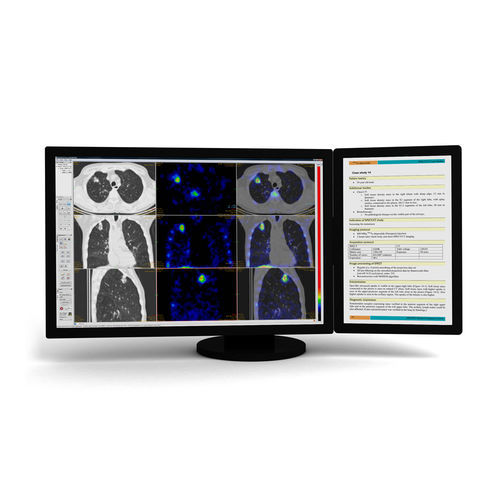

Diese Entwicklung von Mediso beinhaltet die modernsten Bearbeitungsalgorithmen und Werkzeuge zur Evaluierung verschiedener Bildgebungsmodalitäten. Dabei stellt die multimodale Registrierung und Fusion von SPECT, PET, CT und MR eine zentrale Funktionalität der InterView™ FUSION dar. Weiterhin kann die Evaluation mit verschiedenen spezialisierten Darstellungen und automatischen Algorithmen durchgeführt werden.

Statistische Auswertungen können ROI und VOI basiert durchgeführt werden. Ebenso SUV-Darstellungen für PET- und sogar für SPECT-Daten. Eine Vielzahl spezieller Werkzeuge ermöglichen eine detaillierte, schnelle und einfache Auswertung medizinischer Bilder in Kombination mit bestmöglicher graphischer Darstellung und Interaktion in flexiblen Arbeitsbereichen („Workspaces“).

Spezielle Segmentierungsmethoden bieten schnelle und einfache Darstellungen einzelner Organe und Organregionen. Zusätzlich sind arithmetischen Operationen sowie räumliche und frequenzabhängige Filter verfügbar.

Moderne Bilddarstellung

Arbeitsbereiche („Workspaces“) fungieren als virtuelle Screens auf separaten Tabs

Anwenderdefinierte Layouts der Workspaces, mit individuellen Darstellungen